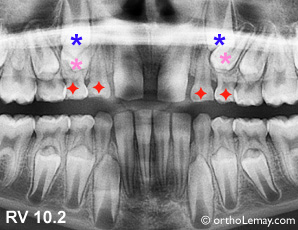

Cas RV : Mauvaise direction des prémolaires supérieures qui bloquent les canines. L’extraction des canines et premières molaires temporaires accélérera et redirigera l’éruption des prémolaires et aidera indirectement les canines.